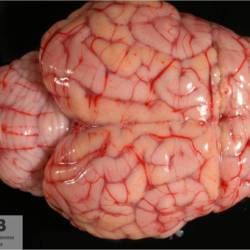

Pàgina anterior de 637 Pàgina següent 3181 total Ovine Specie: Ovine Organ: Brain Lesion: Necrosis Lesion modifier: - Disease: Polioencephalomalacia of ruminants Files/Expedient: Leon3 Position: 253 (1 views) Ovine Specie: Ovine Organ: Brain Lesion: Malacia Lesion modifier: - Disease: Polioencephalomalacia of ruminants Files/Expedient: Leon3 Not viewed Ovine Specie: Ovine Organ: Lung Lesion: Pneumonia Lesion modifier: Pneumonia - Interstitial - Chronic Disease: Maedi-visna Position: 253 (1 views) Ovine Specie: Ovine Organ: Intestine Lesion: Enteritis Lesion modifier: Enteritis - Granulomatous Disease: Paratuberculosis Position: 253 (1 views) Ovine Specie: Ovine Organ: Brain Lesion: Meningocele Lesion modifier: - Disease: - Files/Expedient: Leon2 Not viewed Pàgina anterior de 637 Pàgina següent Títol Select...Avian (Exotic) (110)Avian (Poultry) (76)Bovine (317)Canine (935)Caprine (47)Equine (257)Feline (326)Ferret (19)General (127)Marine mammal (22)Non-human primate (20)Ovine (328)Porcine (379)Rabbit (61)Reptile (38)Rodent (28)Wildlife (91) Format Select...- (60)Abomasum (37)Adrenal gland (10)Blood (7)Blood vessel (50)Body as a whole (19)Bone (57)Bone marrow (21)Brain (93)Cloaca (1)Diaphragm (2)Ear (5)Esophagus (39)Eye (16)Fetus (12)Gallbladder (23)Gizzard (2)Heart (265)Intestine (356)Joint (32)Kidney (443)Larynx (5)Liver (326)Lung (264)Lymph node (91)Mammary gland (10)Mediastinum (1)Muscle (22)Nasal cavity (22)Nerve (7)Omasum (5)Oral cavity (63)Ovary (14)Oviduct (8)Pancreas (7)Parathyroid (5)Penis (10)Peritoneum (65)Pharynx (9)Pituitary gland (6)Placenta (7)Prostate (8)Proventriculus (3)Reticulum (1)Rumen (28)Sinus (7)Skin (181)Spinal cord (15)Spleen (105)Stomach (125)Teeth (1)Testicle (11)Thoracic cavity (31)Thymus (13)Thyroid gland (5)Tongue (32)Tonsils (11)Trachea (11)Urethra (5)Urinay bladder (61)Uterus (27)Vagina (1)Vulva (1)Yolk sac (1) Cobertura Select...- (152)Abomasitis (26)Abscess (27)Acidosis (1)Adenocarcinoma (20)Adenoma (9)Aerosacculitis (6)Agenesis (1)Agnathia (1)Alopecia (7)Amyloidosis (12)Aneurysm (6)Angiectasis (1)Anthracosis (1)Arteritis (11)Arthritis (15)Arthrogryposis (6)Artifact (4)Ascites (13)Atelectasis (8)Atherosclerosis (5)Atresia (1)Atrial septal defect (2)Atrophy (10)Autolysis (7)Bronchitis (6)Bronchopneumonia (26)Cachexia (2)Carcinoma (103)Cardiomyopathy (19)Cellulitis (2)Chemodectoma (4)Cholangiohepatitis (4)Cholangitis (19)Cholecystitis (4)Cholestasis (5)Chondrodysplasia (2)Chondrosarcoma (2)Chronic passive congestion (13)Chylothorax (2)Cirrhosis (6)Coelomitis (3)Coenurus cerebralis (4)Colitis (40)Congestion (17)Conjunctivitis (5)Coronitis (3)Cryptorchidism (3)Cyst (25)Cystitis (24)Dermatitis (69)Diaphragmatic hernia (4)Dilation (28)Discospondylitis (1)Disseminated intravascular coagulation (7)Dyschondroplasia (1)Dysplasia (29)Ectopia cordis (1)Ectopic ureter (1)Edema (55)Emphysema (5)Encephalitis (5)Endocardiosis (14)Endocarditis (26)Endometritis (5)Enteritis (118)Enterolith (6)Epulis (3)Esophagitis (14)Fasciitis (1)Fibrosis (7)Fibrous osteodystrophy (8)Fistula (1)Folliculitis (3)Fracture (2)Gastritis (34)Gingivitis (5)Glioma (8)Glomerulonephritis (21)Glossitis (25)Glycogenosis (1)Gout (8)Granuloma (2)Granulosa cell tumor (4)Hemangioma (9)Hemangiosarcoma (46)Hematoma (8)Hemoglobinuria (2)Hemopericardium (12)Hemoperitoneum (2)Hemorrhage (100)Hemosiderosis (7)Hemothorax (2)Hepatitis (78)Hernia (11)Histiocytosis (3)Hydatid cyst (11)Hydrocephalus (9)Hydrometra (1)Hydronephrosis (22)Hydropericardium (6)Hydrothorax (3)Hydroureter (5)Hyperkeratosis (8)Hyperostosis (4)Hyperplasia (37)Hypertrophy (9)Hypopigmentation (1)Hypoplasia (7)Hypopyon (1)Impaction (6)Infarction (63)Insulinoma (6)Intussusception (5)Jaundice (17)Laminitis (2)Laryngitis (2)Leiomyoma (5)Leukemia (13)Lipidosis (36)Lipoma (7)Lymphadenitis (45)Lymphadenopathy (7)Lymphangiectasia (6)Lymphangitis (5)Lymphoma (221)Malacia (11)Malignant melanoma (15)Mast cell tumor (11)Mastitis (8)Megaesophagus (2)Melanosis (3)Melena (4)Meningioma (6)Meningitis (6)Meningocele (2)Meningoencephalitis (5)Mesothelioma (5)Methemoglobinemia (2)Mineralization (10)Mucocele (5)Mucometra (1)Multilobular bone tumor (1)Mummification (3)Myelofibrosis (1)Myocarditis (4)Myositis (5)Necrosis (81)Nephritis (113)Nephroblastoma (6)Nephrosclerosis (1)Nephrosis (14)Neuritis (1)Obstruction (13)Omasitis (4)Omphalitis (1)Omphalophlebitis (7)Orchitis (4)Osteoarthrosis (5)Osteomyelitis (9)Otitis (2)Palatoschisis (3)Pancreatitis (3)Panniculitis (3)Papilloma (7)Parakeratosis (14)Patent ductus arteriosus (6)Peliosis hepatis (1)Perforation (17)Pericarditis (35)Peritonitis (39)Persistent right aortic arch (1)Pharyngitis (2)Pheochromocytoma (2)Phlebitis (2)Placentitis (6)Pleuritis (21)Pleuropneumonia (24)Pneumonia (109)Pneumothorax (3)Polycystosis (14)Polyp (5)Polyserositis (6)Posthitis (1)Proctitis (4)Prolapse (3)Prostatitis (3)Proventriculitis (1)Pyelonephritis (24)Pyometra (6)Pyothorax (4)Rhinitis (11)Rumenitis (6)Rupture (24)Salpingitis (3)Sarcoma (57)Sclerosis (1)Scoliosis (2)Seminoma (2)Sequestrum (2)Serous atrophy (14)Sinusitis (7)Splenitis (14)Splenomegaly (9)Spondylitis (6)Spondylosis (1)Stenosis (9)Stomatitis (32)Tenosynovitis (2)Teratoma (3)Thricobezoar (2)Thrombosis (16)Tonsilitis (4)Torsion (13)Tracheitis (4)Tympany (7)Typhlitis (8)Typhlocolitis (4)Ulcer (43)Urethritis (1)Urolithiasis (36)Uroperitoneum (1)Uveitis (1)Vasculitis (15)Ventricular septal defect (3)Volvulus (11) Matèria Select... - (14)- (1653)- (152)Abomasitis - Catarrhal (2)Abomasitis - Catarrhal-hemorrhagic (1)Abomasitis - Chronic (1)Abomasitis - Fibrinous-necrotizing (2)Abomasitis - Hyperplasic (5)Abomasitis - Hyperplasic - Chronic (1)Abomasitis - Necrotic (1)Abomasitis - Necrotizing (2)Abomasitis - Ulcerative (5)Adenocarcinoma (9)Aerosacculitis - Granulomatous (1)Amyloidosis - Chronic (1)Arteritis - Necrotic (2)Arteritis - Necrotizing (1)Arthritis - Chronic (4)Arthritis - Fibrinous-purulent (3)Arthritis - Serous (4)Arthritis - Subacute (1)Ascites - Serous (1)Atrophy - Serous (1)Bronchitis - Catarrhal (3)Bronchitis - Suppurative (1)Bronchopneumonia - Catarrhal-purulent (17)Bronchopneumonia - Fibrinous (1)Bronchopneumonia - Granulomatous (1)Bronchopneumonia - Purulent (1)Bronchopneumonia - Suppurative (5)Carcinoma - Adenocarcinoma (33)Carcinoma - Adenocarcinoma - Hepatocellular (2)Carcinoma - Adenocarcinoma - Mucinous (1)Carcinoma - Basosquamous (1)Carcinoma - Cholangiocellular (3)Carcinoma - Hepatocellular (4)Carcinoma - Metastatic (3)Carcinoma - Squamous cell carcinoma (13)Carcinoma - Transitional cell (2)Cardiomyopathy - Dilated (13)Cardiomyopathy - Hypertrophic (6)Cellulitis - Necrotizing (1)Cholangitis - Chronic (8)Cholangitis - Hyperplasic (3)Cholecystitis - Fibrinous-necrotizing (1)Coelomitis - Fibrinous (1)Coelomitis - Granulomatous (1)Colitis - Catarrhal (3)Colitis - Catarrhal-hemorrhagic (1)Colitis - Fibrinous (1)Colitis - Fibrinous-necrotizing (1)Colitis - Fibrinous-necrotizing (Diphtheritic) (6)Colitis - Granulomatous (2)Colitis - Hemorrhagic (4)Colitis - Hemorrhagic-necrotizing (3)Colitis - Necrotizing (2)Colitis - Ulcerative (6)Congestion - Chronic (2)Conjunctivitis - Hyperplasic (1)Conjunctivitis - Purulent (3)Coronitis - Ulcerative (1)Cystitis - Chronic (3)Cystitis - Fibrinous (1)Cystitis - Fibrinous-necrotizing (1)Cystitis - Follicular (1)Cystitis - Hemorrhagic (6)Cystitis - Hemorrhagic-ulcerative (1)Cystitis - Necrotizing (9)Cystitis - Perforated (1)Dermatitis - Granulomatous (14)Dermatitis - Hyperkeratotic (10)Dermatitis - Hyperplasic (proliferative) (1)Dermatitis - Hyperplastic (10)Dermatitis - Necrotizing (4)Dermatitis - Pustular (4)Dermatitis - Ulcerative (2)Dilation - Chronic (1)Discospondylitis - Necrotizing (1)Dysplasia - Follicular (5)Edema - Interstitial (6)Emphysema - Interstitial (1)Encephalitis - Granulomatous (1)Encephalitis - Nonsuppurative (1)Endocardiosis - Mitral (7)Endocardiosis - Mitral - Chronic (5)Endocarditis - Valvular (6)Endocarditis - Valvular - Mitral (7)Endocarditis - Valvular - Pulmonic (1)Endocarditis - Valvular - Subacute (1)Endocarditis - Valvular - Subaortic (5)Endocarditis - Valvular - Tricuspid (4)Endometritis - Purulent (3)Endometritis - Purulent-hemorrhagic (2)Enteritis - Catarrhal (23)Enteritis - Catarrhal - Acute (1)Enteritis - Catarrhal-hemorrhagic (5)Enteritis - Catarrhal-hemorrhagic - Acute (2)Enteritis - Fibrinous (16)Enteritis - Fibrinous - Acute (3)Enteritis - Fibrinous-necrotizing (7)Enteritis - Granulomatous (14)Enteritis - Granulomatous - Chronic (1)Enteritis - Granulomatous - Multifocal (1)Enteritis - Hemorrhagic (17)Enteritis - Hemorrhagic - Acute (1)Enteritis - Hemorrhagic-necrotizing (1)Enteritis - Hyperplasic (proliferative) (4)Enteritis - Necrotizing (4)Enteritis - Necrotizing - Acute (1)Enteritis - Necrotizing - Hemorrhagic (1)Enteritis - Necrotizing-ulcerative (2)Enteritis - Ulcerative (1)Enteritis - Ulcerative-hemorrhagic (1)Esophagitis - Erosive-ulcerative (6)Esophagitis - Necrotizing (4)Esophagitis - Ulcerative (1)Esophagitis - Ulcerative-necrotizing (1)Fasciitis - Fibrinous-purulent (1)Folliculitis - Purulent (2)Gastritis - Catarrhal (2)Gastritis - Chronic (1)Gastritis - Follicular (1)Gastritis - Hemorrhagic (2)Gastritis - Hemorrhagic-necrotizing (1)Gastritis - Hypertrophic (2)Gastritis - Inclusion bodies (1)Gastritis - Mineralization (1)Gastritis - Mycotic (1)Gastritis - Necrotizing (2)Gastritis - Ulcerative (6)Gastritis - Uremic (3)Gingivitis - Erosive (2)Gingivitis - Hyperplasic (proliferative) (1)Gingivitis - Necrotizing (1)Glomerulonephritis - Chronic (7)Glomerulonephritis - Membranoproliferative (3)Glomerulonephritis - Membranoproliferative - Chronic (1)Glomerulonephritis - Membranous (3)Glomerulonephritis - Membranous - Chronic (1)Glomerulonephritis - Proliferative (2)Glomerulonephritis - Subacute (1)Glossitis - Erosive (2)Glossitis - Granulomatous (6)Glossitis - Hyperplasic (1)Glossitis - Hyperplasic (proliferative) (2)Glossitis - Hyperplastic (1)Glossitis - Necrotizing (2)Glossitis - Necrotizing - Focal (1)Glossitis - Ulcerative (6)Glossitis - Ulcerative - Multifocal (1)Glossitis - Ulcerative - Subacute (1)Glycogenosis (1)Granuloma - Eosinophilic (1)Hemangiosarcoma - Metastatic (2)Hemorrhage - Acute (1)Hemorrhage - Subcapsular (3)Hepatitis - Abscess (9)Hepatitis - Acute (3)Hepatitis - Chronic (4)Hepatitis - Chronic interstitial (6)Hepatitis - Granulomatous (7)Hepatitis - Interstitial - Multifocal (1)Hepatitis - Interstitial - Subacute (1)Hepatitis - Necrotizing (17)Hepatitis - Necrotizing - Acute (2)Hepatitis - Necrotizing - Hemorrhagic (1)Hepatitis - Necrotizing - Subacute (1)Hepatitis - Pyogranulomatous (7)Hepatitis - Subacute (4)Hydronephrosis - Chronic (1)Hydropericardium - Chronic (1)Hyperplasia - Erythroid (1)Hyperplasia - Lymphoid (3)Hyperplasia - Myeloid (1)Hyperplasia - Nodular (8)Hypertrophy - Concentric (2)Hypertrophy - Eccentric (3)Infarction - Acute (17)Infarction - Acute - Multifocal (2)Infarction - Chronic (5)Infarction - Chronic - Multifocal (1)Infarction - Subacute (18)Infarction - Subacute - Focal (2)Laminitis - Chronic (2)Laryngitis - Necrotic (1)Laryngitis - Necrotizing (1)Leukemia - Lymphoid leukemia (2)Leukemia - Non-lymphoid leukemia (6)Lipidosis - Multifocal (1)Lipidosis - Panlobular (1)Lipidosis - Panlobular - Generalized (2)Lymphadenitis - Granulomatous (24)Lymphadenitis - Granulomatous - Chronic (3)Lymphadenitis - Hemorrhagic (1)Lymphadenitis - Necrotizing (5)Lymphadenitis - Necrotizing (caseous) (11)Lymphangitis - Granulomatous (1)Lymphangitis - Purulent (1)Lymphangitis - Ulcerative (1)Lymphoma - Alimentary lymphoma (7)Lymphoma - Cutaneous lymphoma (6)Lymphoma - Lymphosarcoma (2)Lymphoma - Mediastinal lymphoma (1)Lymphoma - Multicentric lymphoma (29)Malignant melanoma - Malignant (1)Malignant melanoma - Metastatic (1)Mast cell tumor - Metastatic (1)Mastitis - Fibrinous-purulent (2)Mastitis - Necrotic (1)Mastitis - Purulent (3)Mastitis - Suppurative (1)Meningitis - Fibrinous-purulent (2)Meningitis - Purulent (4)Meningoencephalitis - Necrotizing (3)Meningoencephalitis - Nonsuppurative (2)Mineralization - Metastatic (4)Myocarditis - Fibrous - Chronic (1)Myocarditis - Granulomatous (1)Myositis - Purulent (2)Necrosis - Acute (1)Necrosis - Cortical (5)Necrosis - Follicular (1)Necrosis - Papillary (8)Necrosis - Papillary - Acute (3)Necrosis - Subacute (3)Necrosis - Tubular (6)Nephritis - Embolic (2)Nephritis - Embolic suppurative (7)Nephritis - Granulomatous (27)Nephritis - Granulomatous - Chronic (1)Nephritis - Granulomatous - Multifocal (1)Nephritis - Interstitial (6)Nephritis - Interstitial - Acute (4)Nephritis - Interstitial - Chronic (41)Nephritis - Interstitial - Subacute (12)Nephritis - Purulent (7)Nephritis - Purulent - Acute (2)Nephritis - Purulent - Multifocal (3)Nephrosis - Cholemic (3)Nephrosis - Hemoglobinuric (10)Omasitis - Fibrinous-necrotizing (1)Omasitis - Hyperkeratotic (1)Omasitis - Necrotizing (2)Omphalophlebitis - Fibrinous-purulent (2)Omphalophlebitis - Purulent (3)Orchitis - Necrotizing (1)Osteomyelitis - Necrotizing (7)Osteomyelitis - Purulent (2)Otitis - Necrotizing (1)Otitis - Proliferative (1)Pancreatitis - Acute (1)Pancreatitis - Chronic (1)Pancreatitis - Granulomatous (1)Panniculitis - Fibrinous-purulent (1)Panniculitis - Necrotic (1)Panniculitis - Parasitic (1)Perforation - Acute (2)Pericarditis - Fibrinous (19)Pericarditis - Fibrinous - Subacute (1)Pericarditis - Fibrinous-necrotizing (1)Pericarditis - Fibrinous-purulent (3)Pericarditis - Fibrous (1)Pericarditis - Fibrous - Chronic (1)Pericarditis - Gangrenous (6)Pericarditis - Granulomatous (1)Pericarditis - Granulomatous - Chronic (2)Peritonitis - Acute (1)Peritonitis - Fibrinous (11)Peritonitis - Fibrinous - Subacute (1)Peritonitis - Fibrinous-purulent (5)Peritonitis - Fibrous (3)Peritonitis - Granulomatous (6)Peritonitis - Purulent (1)Peritonitis - Purulent-hemorrhagic (1)Peritonitis - Pyogranulomatous (3)Pharyngitis - Fibrinous-necrotizing (1)Pharyngitis - Ulcerative (1)Pheochromocytoma - Metastatic (1)Phlebitis - Purulent (1)Placentitis - Fibrinous-necrotizing (1)Placentitis - Necrotic (1)Placentitis - Necrotizing (1)Pleuritis - Chronic (1)Pleuritis - Fibrinous (3)Pleuritis - Fibrinous-purulent (2)Pleuritis - Fibrous (2)Pleuritis - Granulomatous (3)Pleuritis - Hyperplastic (2)Pleuritis - Purulent (2)Pleuritis - Pyogranulomatous (1)Pleuropneumonia - Fibrinous (13)Pleuropneumonia - Fibrinous-necrotizing (5)Pleuropneumonia - Granulomatous (2)Pleuropneumonia - Hemorrhagic-necrotizing (4)Pneumonia - Aspiration (11)Pneumonia - Bronchointerstitial (4)Pneumonia - Bronchointerstitial - Subacute (1)Pneumonia - Embolic (5)Pneumonia - Granulomatous (37)Pneumonia - Granulomatous - Multifocal (4)Pneumonia - Hemorrhagic-necrotizing (2)Pneumonia - Interstitial (7)Pneumonia - Interstitial - Acute (8)Pneumonia - Interstitial - Chronic (6)Pneumonia - Interstitial - Subacute (15)Pneumonia - Necrotizing (2)Pneumonia - Pyogranulomatous (2)Pneumonia - Verminous (5)Polyserositis - Fibrinous (6)Polyserositis - Fibrous (1)Proctitis - Fibrinous-necrotizing (1)Proctitis - Parasitic (2)Prostatitis - Purulent (1)Pyelonephritis - Acute (2)Pyelonephritis - Chronic (3)Rhinitis - Catarrhal (2)Rhinitis - Fibrinous (1)Rhinitis - Granulomatous (4)Rhinitis - Purulent (3)Rumenitis - Acute (1)Rumenitis - Erosive (1)Rumenitis - Necrotizing (1)Rupture - Acute (3)Sarcoma - Fibrosarcoma (12)Sarcoma - Hemangiosarcoma (11)Sarcoma - Histiocytic (7)Sarcoma - Metastatic (1)Sarcoma - Multilobular tumor of bone (1)Sequestrum - Chronic (2)Sinusitis - Suppurative (1)Splenitis - Granulomatous (8)Splenitis - Granulomatous - Chronic (1)Splenitis - Necrotizing (3)Splenitis - Necrotizing (caseous) (2)Spondylitis - Necrotizing (2)Stenosis - Intestinal (1)Stenosis - Valvular - Subaortic (4)Stomatitis - Erosive (12)Stomatitis - Erosive-ulcerative (3)Stomatitis - Fibrinous-necrotizing (1)Stomatitis - Fibrinous-necrotizing (Diphtheritic) (1)Stomatitis - Granulomatous (1)Stomatitis - Hyperplasic (1)Stomatitis - Hyperplasic (proliferative) (1)Stomatitis - Necrotizing (2)Stomatitis - Ulcerative (5)Stomatitis - Ulcerative - Multifocal (1)Stomatitis - Ulcerative-necrotizing (1)Tonsilitis - Necrotizing (4)Torsion - Acute passive hyperemia (5)Tracheitis - Catarrhal (3)Tracheitis - Fibrinous (1)Tracheitis - Granulomatous (1)Typhlitis - Catarrhal (1)Typhlitis - Fibrinous-necrotizing (2)Typhlitis - Hemorrhagic (2)Typhlitis - Ulcerative-hemorrhagic (1)Typhlocolitis - Fibrinous-necrotizing (2)Typhlocolitis - Proliferative (1)Ulcer - Chronic (6)Ulcer - Multifocal (2)Ulcer - Mycotic (1)Ulcer - Perforated (6)Urethritis - Hemorrhagic (1)Urolithiasis - Chronic (2)Uveitis - Granulomatous (1)Vasculitis - Granulomatous (1)Vasculitis - Necrotizing (1) Editor Select...- (1970)Acidosis (2)Actinobacillosis (Pleuropneumonia) (11)Aelurostrongylosis (2)African horse sickness (13)African swine fever (14)Alopecia X (1)Anaplasmosis (4)Anthrax (2)Aortic thromboembolism (feline) (7)Ascariasis (15)Aspergillosis (18)Atopic dermatitis (1)Atrophic rhinitis (3)Babesiosis (6)Blackhead (1)Bluetongue (11)Border disease (2)Bovine viral diarrhea (21)Brucellosis (2)Candidiasis (5)Canine distemper (14)Caprine arthritis-encephalitis (2)Capture myopathy (1)Cardiac insufficiency (17)Caseous lymphadenitis (7)Chlamydiosis (2)Classical swine fever (19)Clostridiosis (19)Coccidiosis (9)Coenurosis (4)Colibacillosis (21)Contagious ecthyma (7)Copper toxicosis (11)Cowdriosis (Heartwater) (3)Cryptococcosis (3)Cryptosporidiosis (2)Cysticercosis (23)Demodicosis (1)Diabetes (1)Dicrocoeliosis (5)Dictyocaulosis (4)Dirofilariasis (7)Discoid lupus erythematosus (3)Echinococcosis (17)Edema disease (7)Egg drop syndrome (1)Encephalitozoonosis (5)Enterotoxemia (1)Enzootic bovine leukosis (46)Epitheliogenesis imperfecta (3)Equine rhinopneumonitis (2)Equine verminous arteritis (strongylosis) (7)Erysipelas (5)Exudative epidermitis (7)Fasciolasis (11)Feline eosinophilic dermatoses (1)Feline hepatic lipidosis (8)Feline histiocytosis (4)Feline infectious peritonitis (38)Feline leukemia (4)Feline lower urinary tract disease (3)Feline panleukopenia (16)Feline viral rhinotracheitis (1)Flea allergy dermatitis (1)Foot and mouth disease (2)Gasterophilosis (4)Glasser's disease (15)Gousiekte (4)Gout (6)Haemonchosis (9)Hemolytic anemia (4)Hemorrhagic diathesis (1)Hepatic insufficiency (11)Hepatosis dietetica (7)Herpesvirosis (6)Hyperadrenocorticism (7)Hyperparathyroidism (10)Hypertrophic osteopathy (6)Hypervitaminosis D (1)Hypodermosis (1)Inclusion body hepatitis (4)Infectious bovine rhinotracheitis (5)Infectious bronchitis (5)Infectious canine hepatitis (13)Influenza (4)Juvenile nephropathy (8)Lamb dysentery (4)Leishmaniasis (28)Leptospirosis (1)Leukosis (5)Listeriosis (4)Lumpy skin disease (3)Maedi-visna (4)Malignant catarrhal fever (12)Mange (6)Mannheimiosis (5)Marek's disease (7)Metabolic bone disease (2)Mucoid enteropathy (5)Mulberry heart disease (5)Myasis (1)Mycobacteriosis (22)Mycosis fungoides (6)Myxomatosis (3)Necrobacillosis (5)Neonatal isoerythrolysis (6)Nocardiosis (4)Oestrosis (2)Onchocerciasis (1)Osteochondrosis (1)Ostertagiosis (6)Ovine pulmonary adenocarcinoma (5)Oxyuriasis (1)Pacheco's disease (4)Papillomatosis (6)Paratuberculosis (18)Parvovirosis (17)Pasteurellosis (11)Pemphigus foliaceus (1)Periodontal disease (1)Polioencephalomalacia of ruminants (4)Polyarteritis nodosa (3)Polycystic kidney disease (13)Porcine circovirosis (11)Porcine dermatitis and nephropathy syndrome (9)Porcine proliferative enteropathy (4)Porcine reproductive and respiratory syndrome (6)Porcine stress syndrome (1)Pox (13)Pregnancy toxemia (3)Proventricular dilatation disease (2)Pseudotuberculosis (yersiniosis) (2)Psittacine beak and feather disease (PBFD) (5)Pyoderma (4)Q fever (4)Rabbit hemorrhagic disease (2)Renal insufficiency (12)Reticuloendotheliosis (2)Rhodococcosis (1)Rickets (1)Rinderpest (2)Salmonellosis (34)Sarcosporidiosis (2)Schmallenberg (7)Septicemia (23)Spirocercosis (11)Streptococcosis (5)Strongylosis (1)Swine dysentery (5)Systemic coronavirosis (5)Tetralogy of Fallot (5)Theileriosis (13)Thromboembolism (5)Toxoplasmosis (11)Transmissible viral proventriculitis (1)Traumatic reticuloperitonitis (3)Traumatism (16)Tuberculosis (58)Ulcerative lymphangitis (1)Uremic syndrome (20)Viral arthritis (6)White muscle disease (9)Wobbler syndrome (2)Xanthomatosis (1)Zygomycosis (4) Idioma Select...- (1180)Bacterial (501)Degeneration (106)Fungal (46)Hemodynamic (112)Idiopathic (22)Inflammation (58)Malformation (88)Neoplasia (343)Nutritional (41)Parasitic (243)Physical/Chemical (93)Toxic (44)Viral (304) Ítem destacat Avian (Poultry) Broilers. Livers are swollen, pale, friable with petechial or echymotic hemorrhages. Adenovirus (group I).